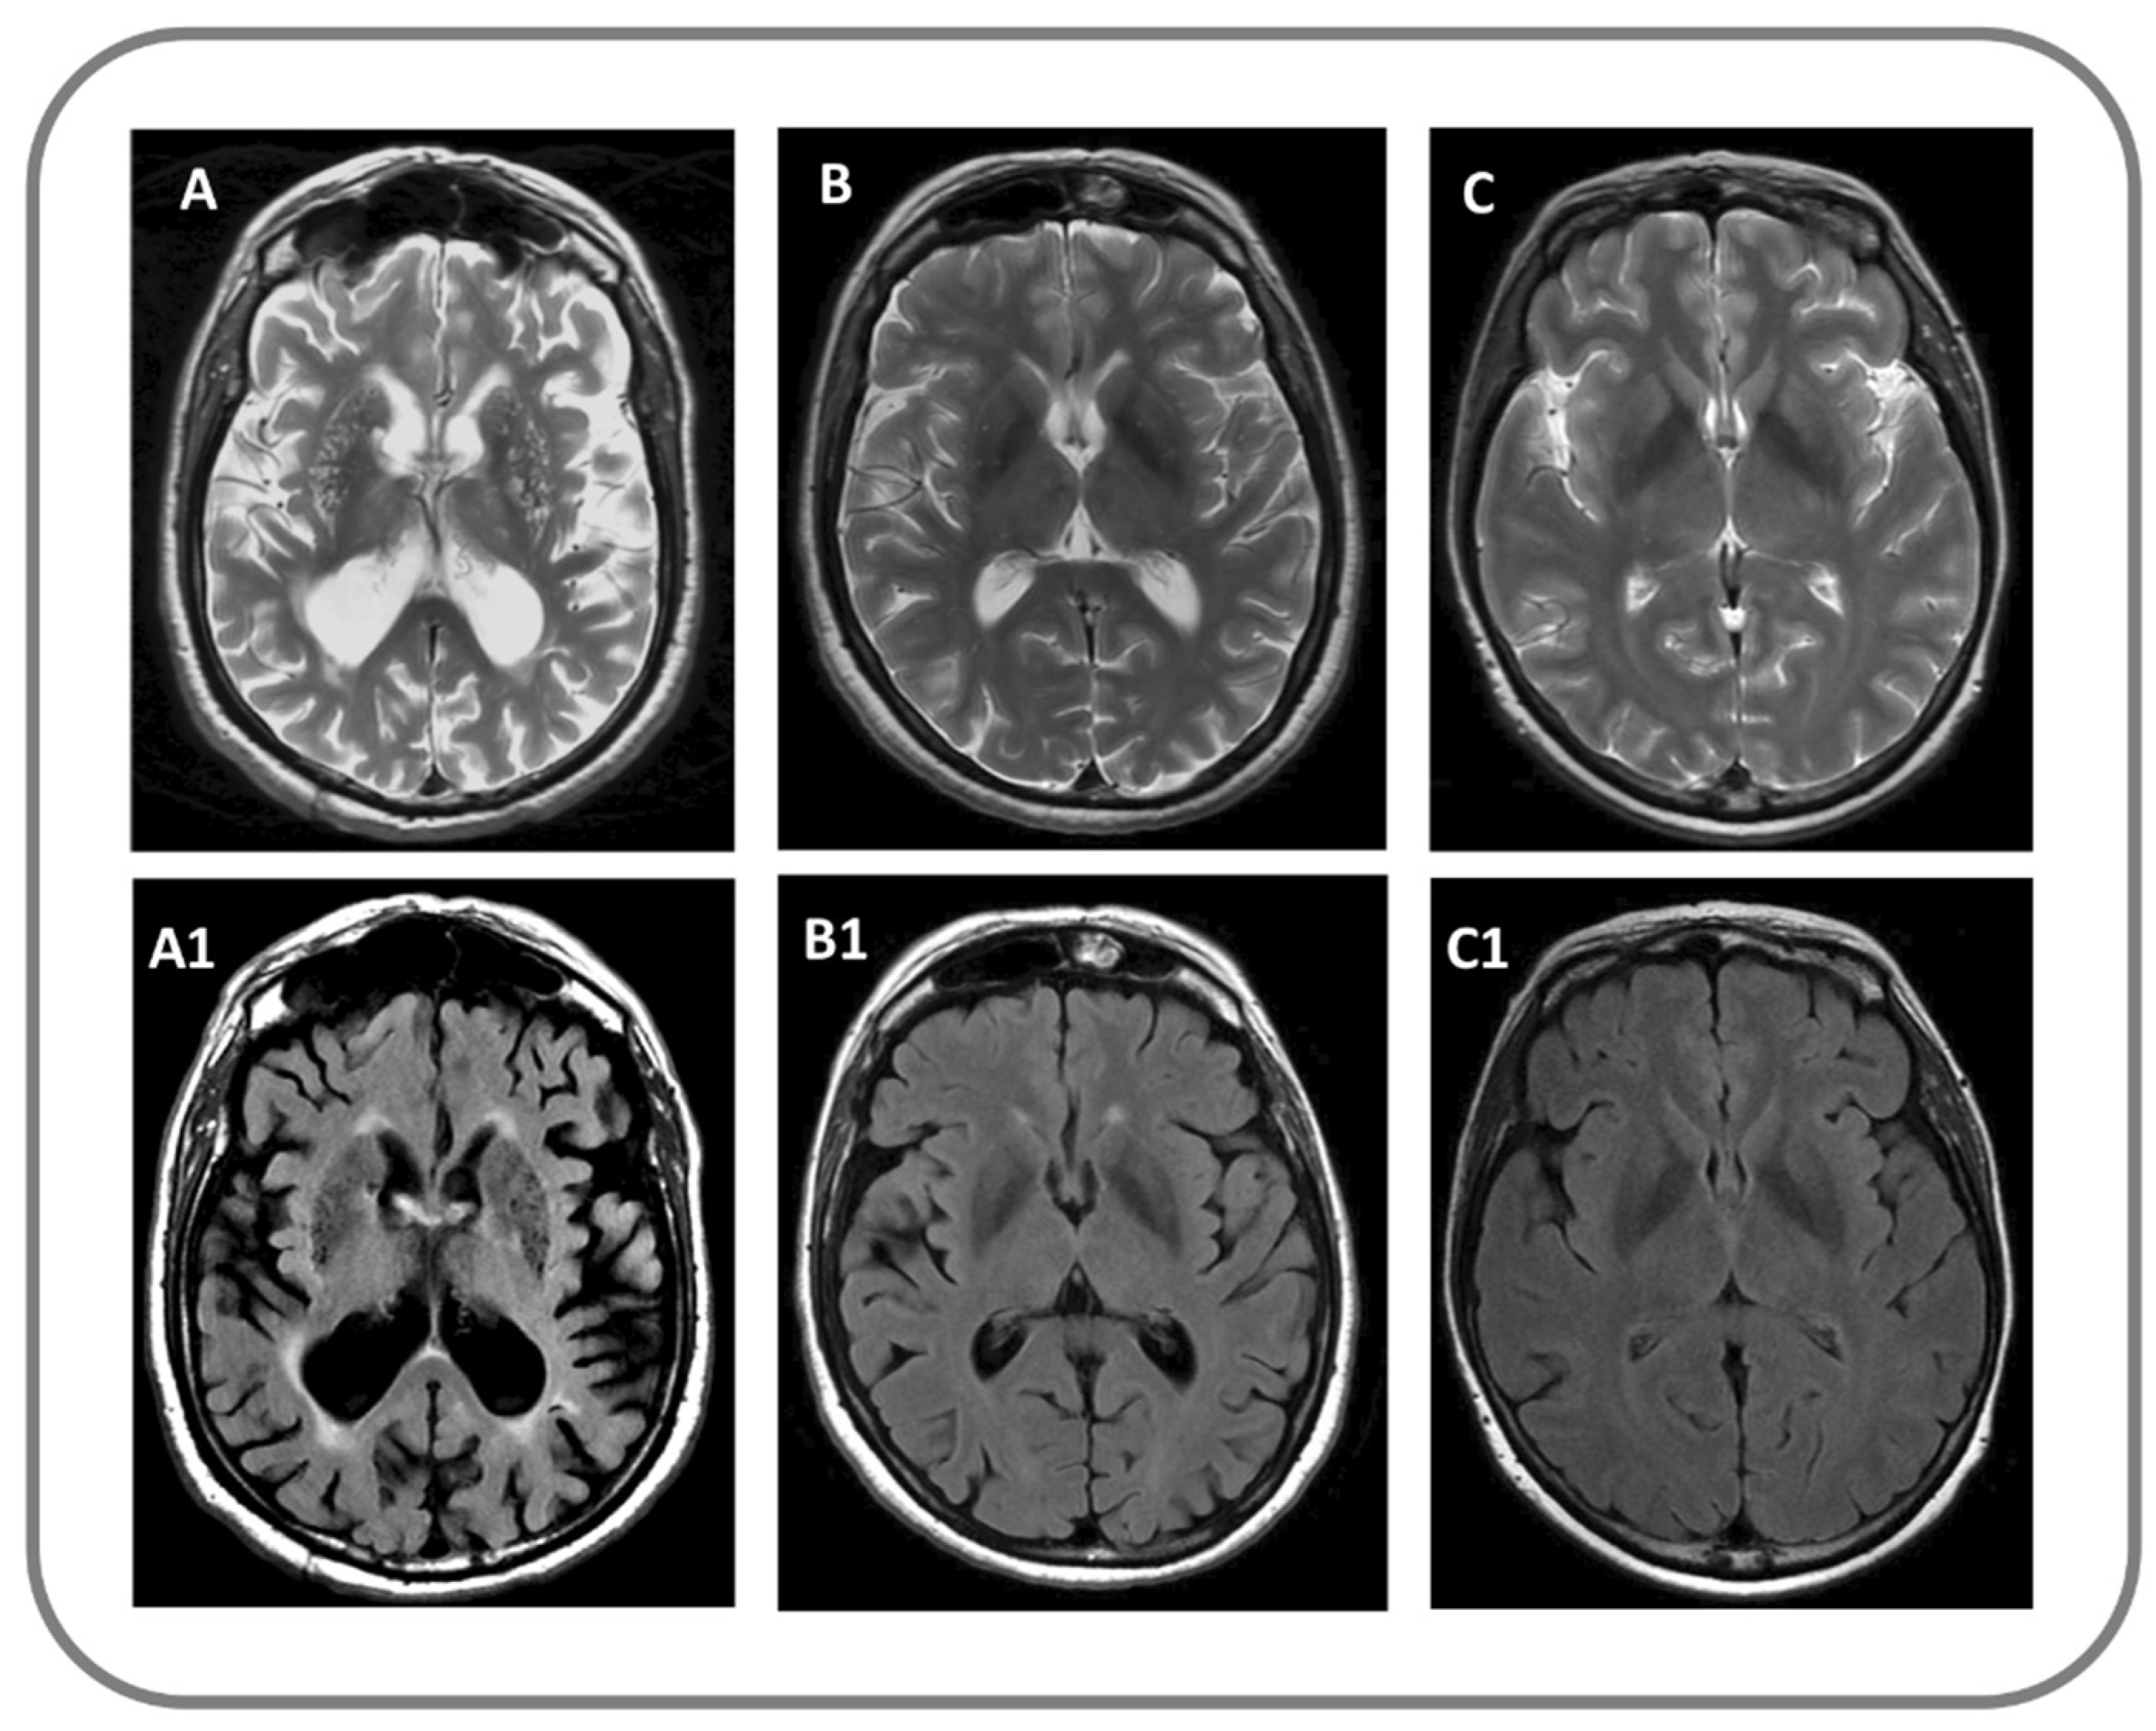

2.2. MRI Protocol, Data Processing and Analysis